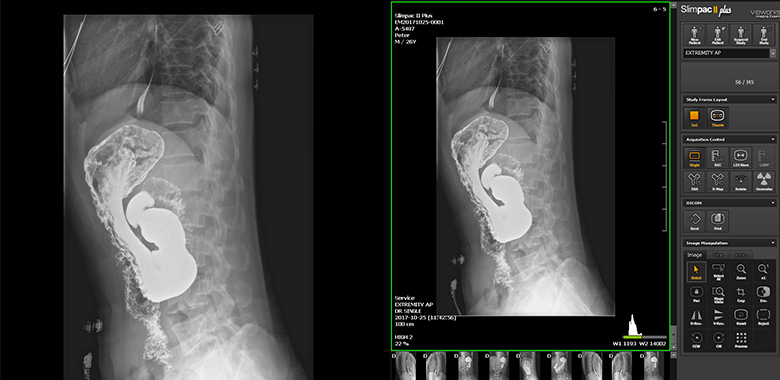

Exclusive Radiography & Fluoroscopy(RF) Viewer

Slimpac Ⅱ Plus is an image viewer program with specialized modules to acquire, adjust, and manage diagnostic images created by the VIVIX-D Series.

Radiography Image Processing

- Radio Image Process(Slimpac Process) gamma, edge enhancement, Simplified Lumbar Degeneration Classification(SLDC), etc.

- XIPL(X-ray Image Processing Library) auto crop, grid suppression, contrast / brightness option, Look Up Table(LUT), etc.

- 3 Types of Image Processing soft, normal, hard predefined parameters for personal preference